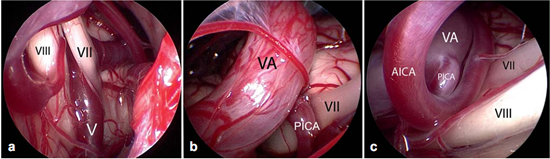

面神经的微血管减压术是治愈面肌痉挛的唯一治疗选择。手术旨在去除出脑干区(REZ)血管对神经的压迫。血管对神经造成压迫是主要病因。手术需全身麻醉。为了观察手术过程中耳蜗的和面部的神经的改变,需要在手术进行过程中对面神经的肌电图(EMG)和听觉诱发电位(auditory evoked potentials)进行监测。使用乙状窦后入路开颅术(retrosigmoidal craniotomy)(figure 3)暴露小脑桥脑角。在随后的手术过程中,尤其注意检查出脑干区的面神经(figure 5),该面神经发源于脑干。内窥镜检查法对于确定血管压迫位置很有效(figure 4,6)。因此,在米兰·(milan)医院把内窥镜检查法作为指导程序。

Figure 6不同类型的血管压迫。Ⅶ=面神经;Ⅷ=蜗神经

a:由靠近脑干的静脉(Ⅴ)所造成的压迫;

b:椎动脉(VA)和小脑右下动脉(PICA)共同压迫;

c:椎动脉(VA)、下移的小脑右下动脉(PICA)和小脑前下动脉(AICA)共同压迫。